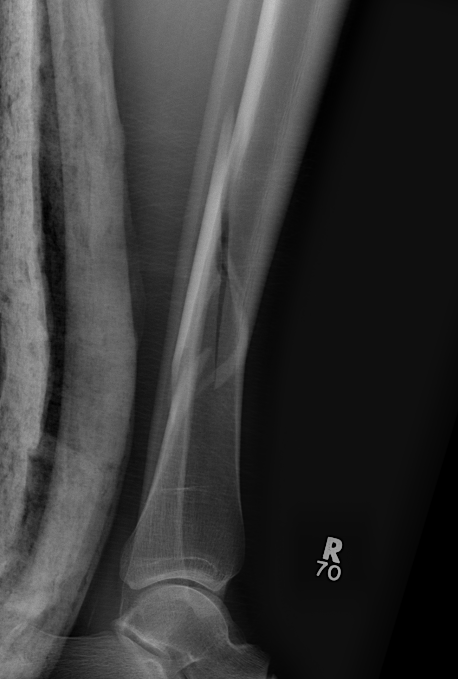

Posterior Malleolar Fractures

- occult in 70%

- especially with spiral distal tibial fractures

Wang et al. J Orthop Surg Res 2021

- systematic review

- incidence 70% occult fractures